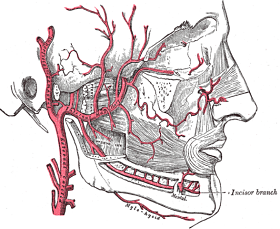

Desde el inicio de su recorrido en la articulación temporo-mandibular, la arteria maxilar entra en la fosa infratemporal del cráneo, un área está formada por los huesos esfenoides, maxilar, temporal y mandibular.

Luego continúa su trayecto hacia la fosa pterigopalatina, donde se relaciona con el músculo pterigoideo lateral, siguiendo un recorrido paralelo a él.

– Segmento 1: también conocido como segmento óseo. Se ubica en el cuello de la mandíbula. En este pequeño trayecto la arteria da cinco ramas que se encargan de nutrir estructuras internas del cráneo.

– Segmento 2: denominado segmento muscular debido a que en esta parte sigue paralelamente al músculo pterigoideo lateral. Esta sección da cuatro ramos vasculares a estructuras bucales y también es la principal irrigación del músculo pterigoideo lateral.

– Segmento 3: llamado segmento pterigopalatino, es la porción que se encuentra anterior al músculo pterigoideo lateral y da ocho ramos vasculares que se encargan de irrigar el paladar, los músculos de la masticación y la región infraorbitaria.